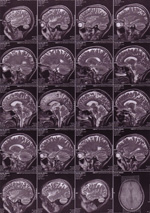

A suggested look into my brain – which I simply think fascinating and thus could not resist to put it here – wants to follow up eventual gaps in my mind ..

So far gaping jumps occur only here on this blog ; ) … and I hope they will be reduced from now on significantly … : )

UPDATE: .. and to find out almost immediately – I am not alone with that kind of idea … perma7k : )